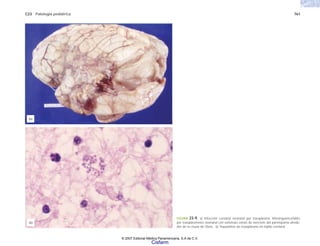

* Las pruebas sugieren que estas neoplasias se asocian con nue-

vos miembros del grupo de los virus herpes.